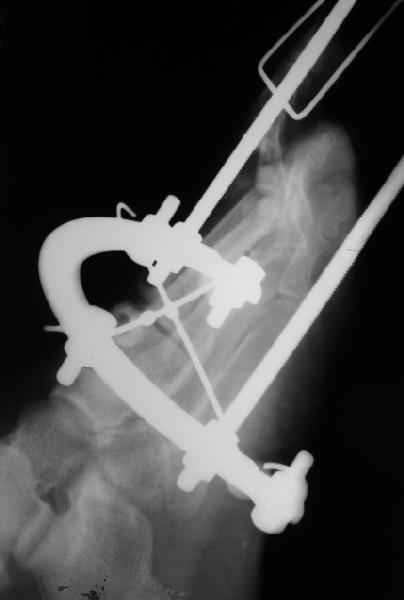

Та же проблема - по крайней мере на снимке в аппарате (фас) отчетливо видно перелом ее головки.

3 кстати, Вы перелом пкрвой плюсневой видите? В каком месте и на каком снимке?

Вот головка более прицельно.

Вот теперь вижу :)

предлагаю. Все то же самое плюс по обстоятельствам, в зависимости от внутриоперационных находок- либо ничего не делаем, либо фиксируем фрагмент спицей ( можно даже адсорбируемой - получим пласмассоостеосинтез:)) или микрошурупом, либо - если вправление пойдет совсем плохо - все же как минимум восьмая неделя - эксцизионная пластика сустава .